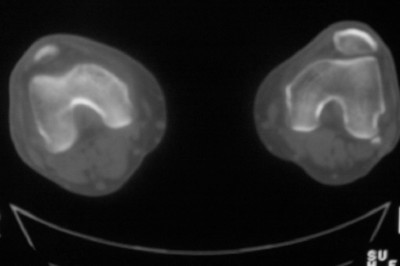

标题: CT8024:会诊!!!男 60 岁 双漆关节疼痛半年,进行性加重 [打印本页]

患者男 60 岁 双漆关节疼痛半年,进行性加重.

膝关节退行性变

膝关节退行性变,最好是结合x线平片

右侧髁间隆突变尖,软骨下假囊肿形成,结合病人年龄较大,首先考虑退行性骨关节病。关节周围软组织未见明显异常,病人单单一双膝关节出现症状,不太支持类风湿性关节炎,可结合化验室检查。